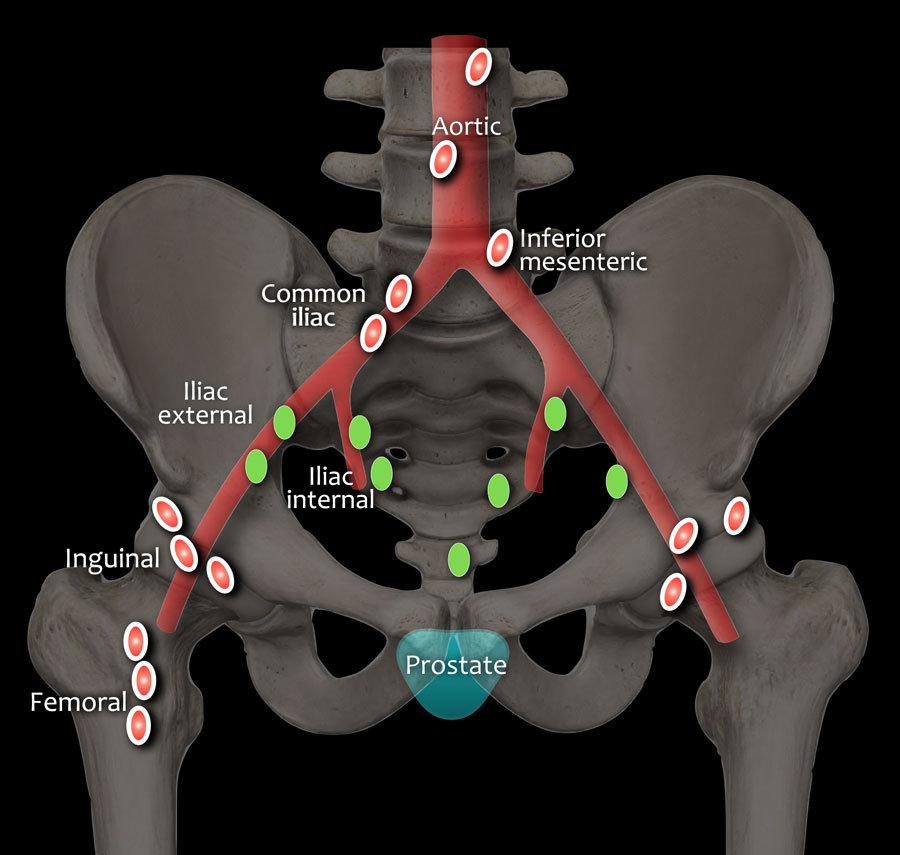

The Spread of Prostate Cancer – Prostate Cancer Research Centre